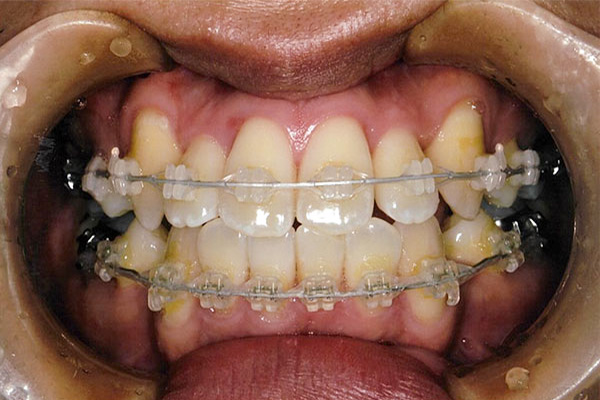

2年2ヶ月後